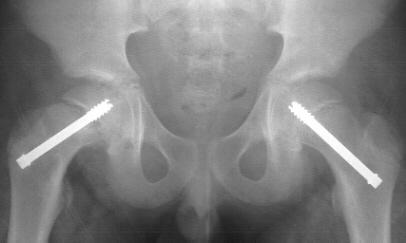

normal. At his three-month follow-up visit, the patient complained of a

two week history of vague left hip pain. AP

and frog-leg lateral radiographs revealed a grade 1 left slipped capital

femoral epiphysis. He had an in situ pinning of his left hip the next day

without complications

.